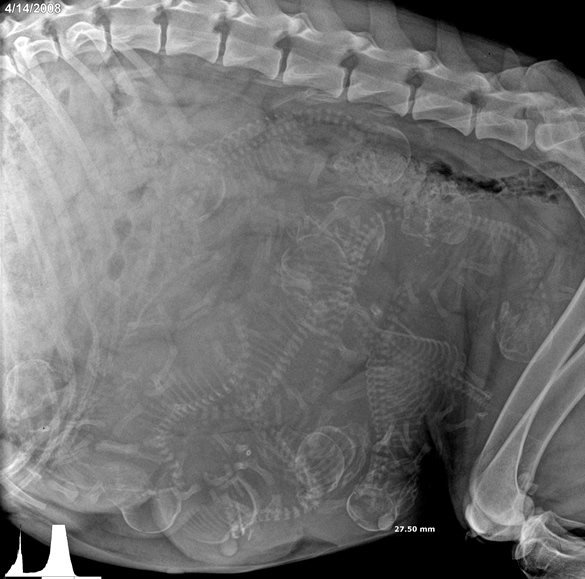

Еще одна беременная кошка.